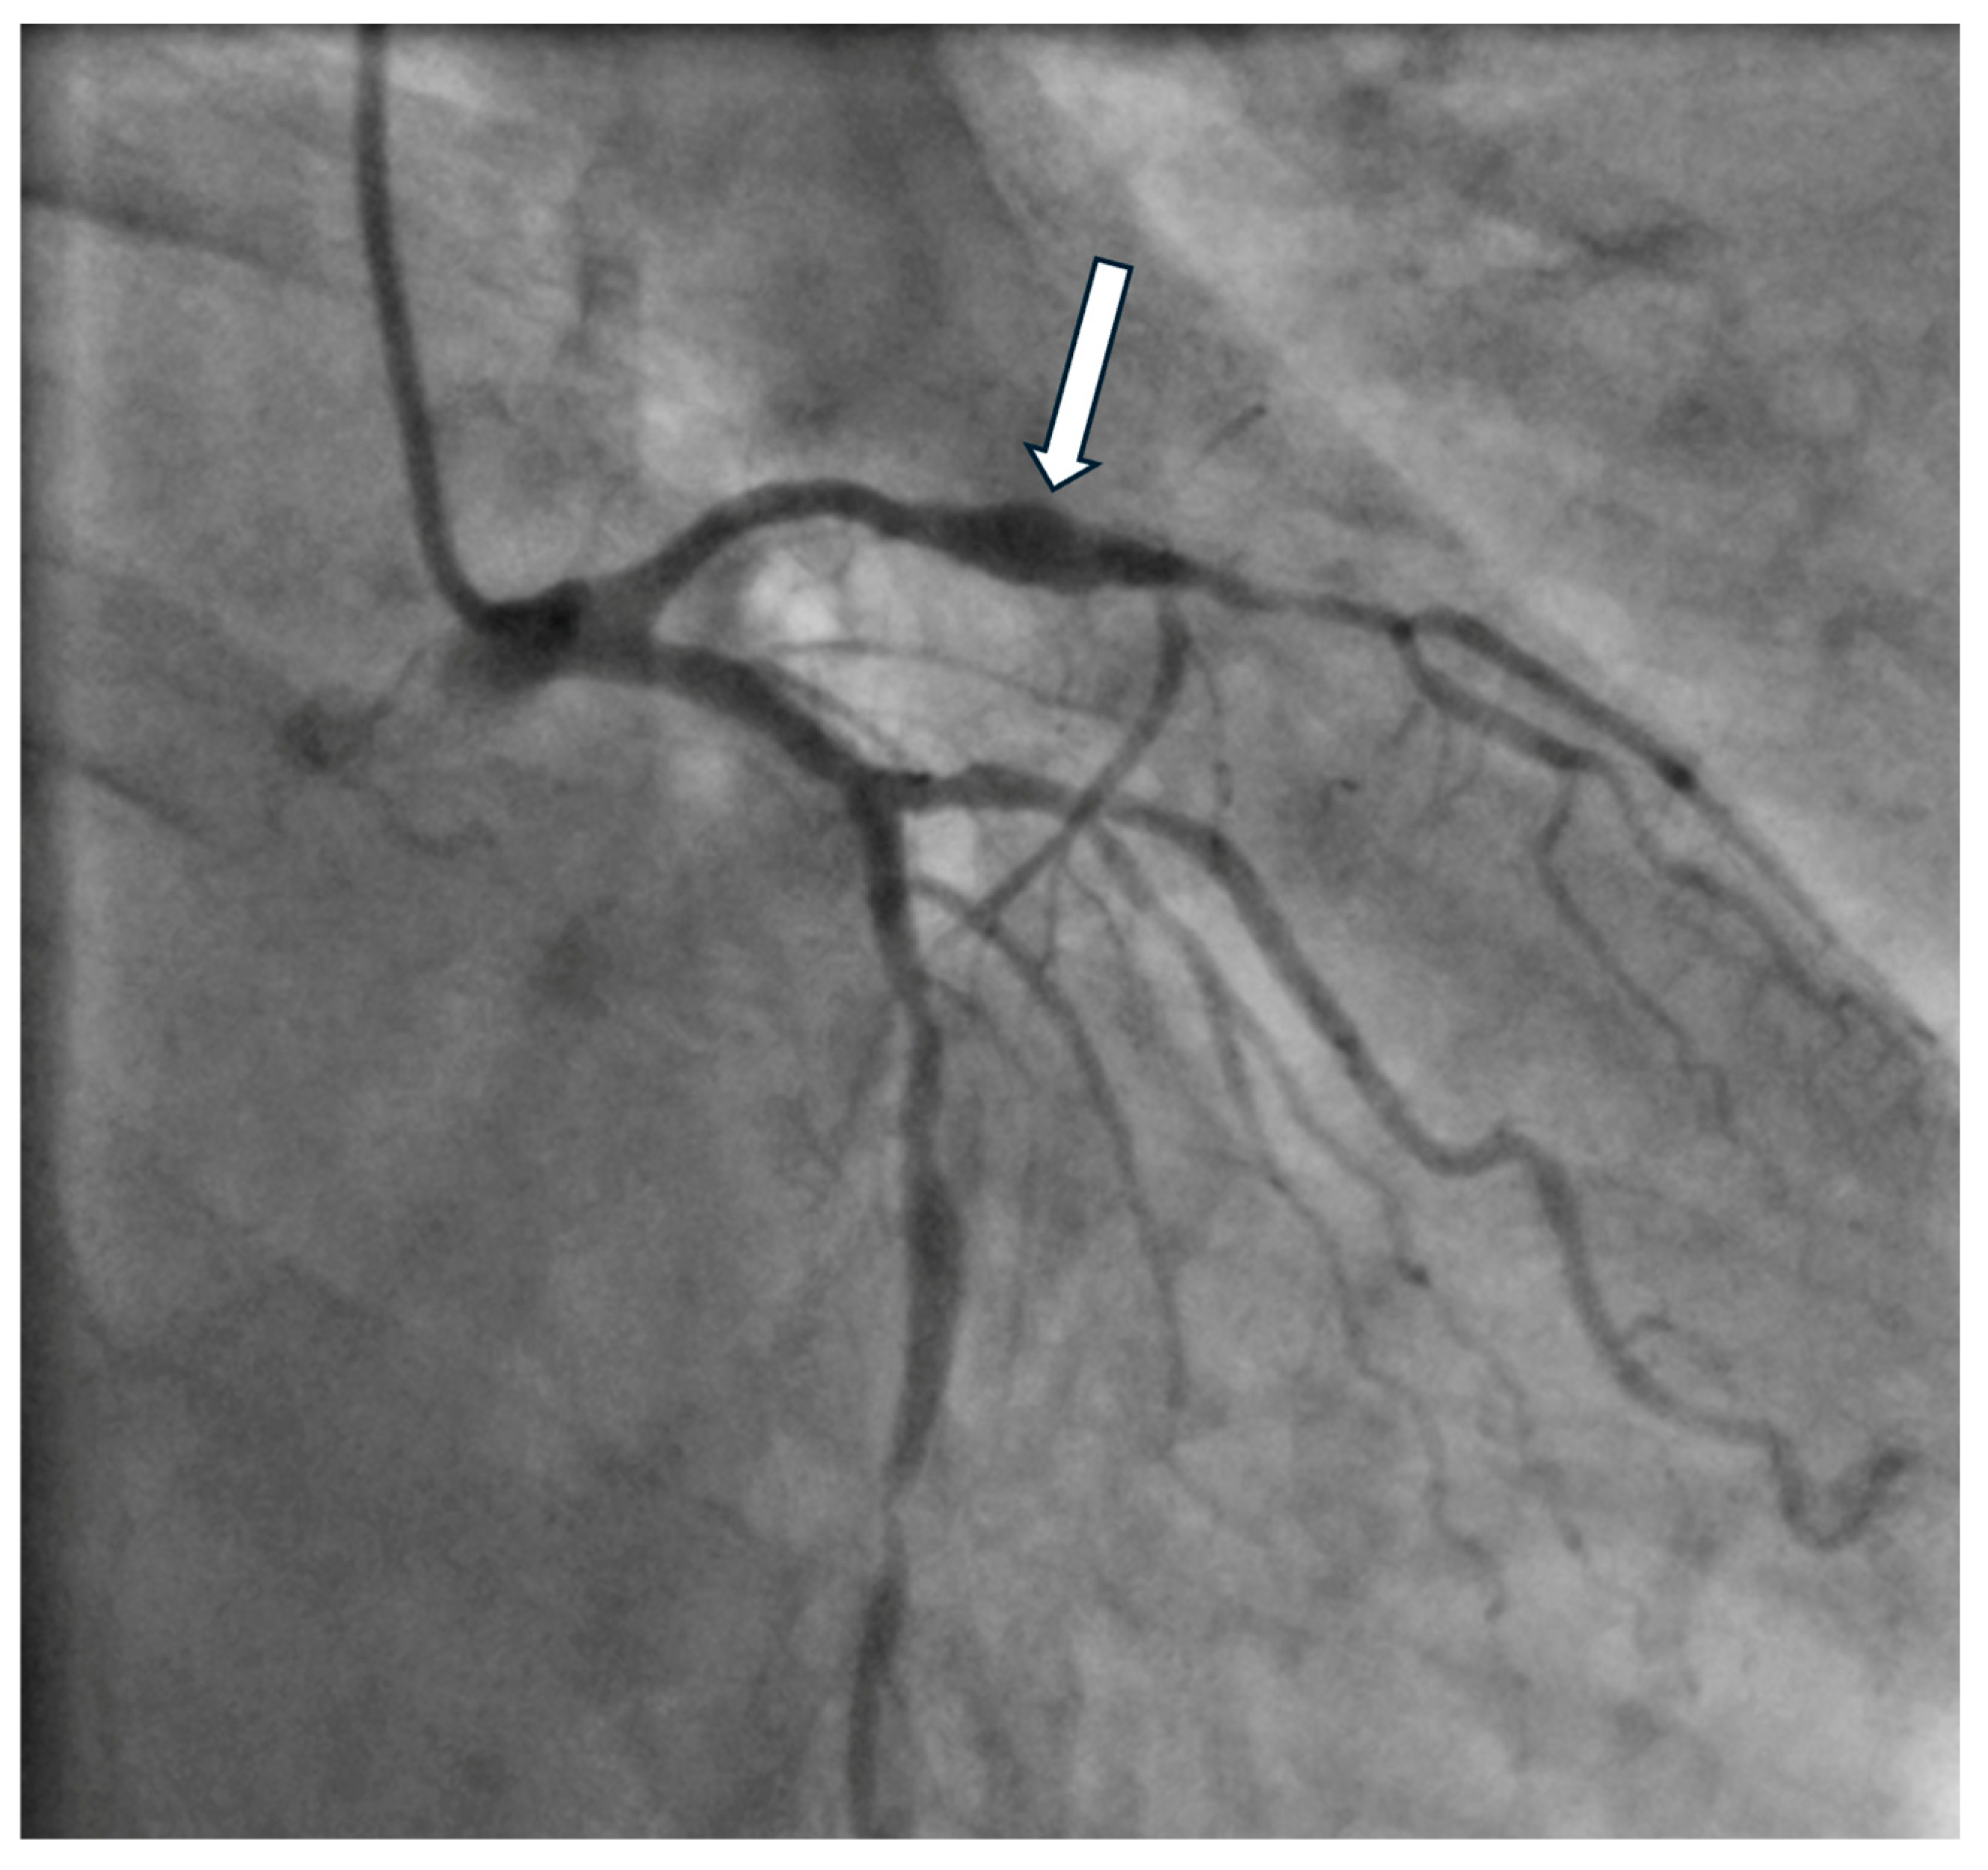

- Manginas, A.; Cokkinos, D.V. Coronary artery ectasias: Imaging, functional assessment and clinical implications. Eur. Heart J. 2006, 27, 1026–1031. [Google Scholar] [CrossRef]

- Murthy, P.A.; Mohammed, T.L.; Read, K.; Gilkeson, R.C.; White, C.S. MDCT of coronary artery aneurysms. AJR Am. J. Roentgenol. 2005, 184 (Suppl. 3), S19–S20. [Google Scholar] [CrossRef]

- Johnson, P.T.; Fishman, E.K. CT Angiography of Coronary Artery Aneurysms: Detection, Definition, Causes, and Treatment. Am. J. Roentgenol. 2010, 195, 928–934. [Google Scholar] [CrossRef]